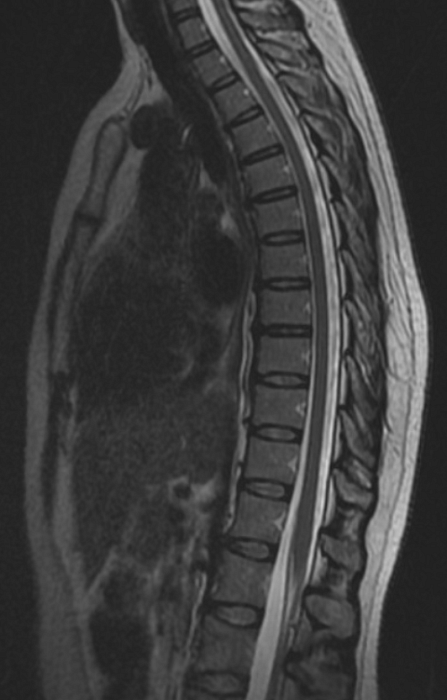

МРТ грудного отдела позвоночника

Магнитно-резонансная томография грудного отдела позвоночника – важный метод исследования, который позволяет оценить состояние грудного отдела позвоночника.